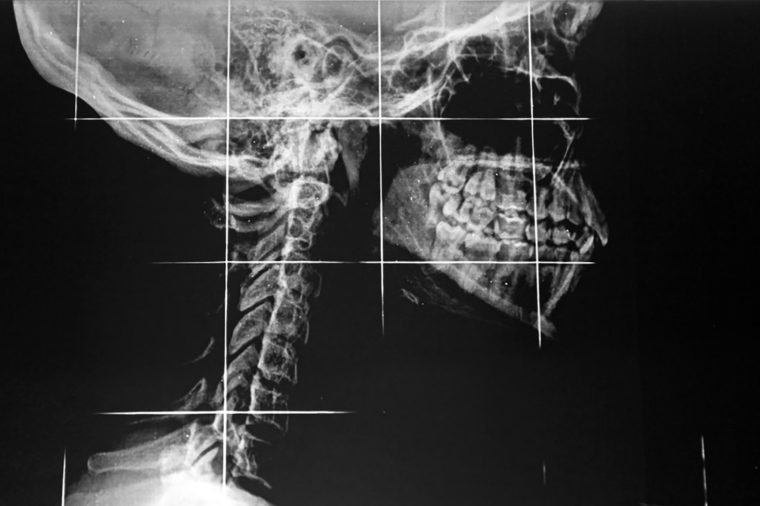

Temporomandibular joint disorder, abbreviated as TMD (also known as TMJ), affects the joints that connect the jawbone to the skull. It is one of the common jaw pain causes that is characterized by pain and restricted movement. It is not life-threatening, but its symptoms can significantly affect the quality of life. Typical indications of TMD are pain and tenderness in the jaw joint area, the neck, the shoulders, the face, and the ear. But symptoms go beyond pain. “A patient can also experience locked jaw, hear a cracking or clicking sound when the mouth is opened or closed, and have an uncomfortable bite and inflamed side of the face,” explains dentist Danica Lacson of Hawaii Family Dental. A physical exam will allow your dentist to diagnose TMD and determine its probable cause. Traditional treatments for TMD include medications, a night guard, and dental fixes to correct bite problems and balance biting surfaces, according to Lacson. Patients can also try home remedies, including over-the-counter medications, heat or cold packs, and relaxation therapy to manage the pain. Here are more home remedies that are proven to work.